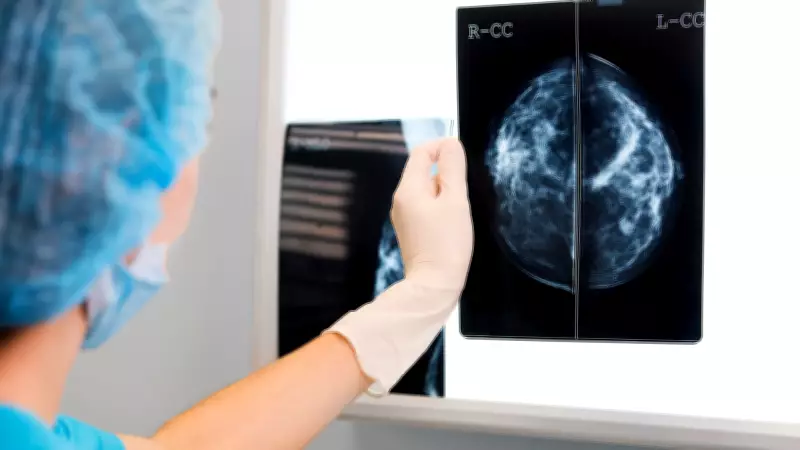

The Alberta government has announced a significant expansion of its breast cancer screening program, lowering the age of eligibility for free mammograms. This proactive health policy change aims to enhance early detection rates and improve survival outcomes for women across the province.

By reducing the age threshold, Alberta health officials seek to identify breast cancer at earlier, more treatable stages. Early detection is crucial, as it often leads to less aggressive treatments and higher survival rates. The move aligns with growing medical evidence supporting screening for younger demographics, particularly those with risk factors or family histories of the disease.

This policy shift reflects a commitment to preventive healthcare, potentially reducing long-term healthcare costs by addressing cancers before they advance. Health experts emphasize that regular screenings can save lives by catching abnormalities that might otherwise go unnoticed until symptoms develop.

The expanded eligibility is expected to benefit thousands of additional women, providing them with access to vital screening services without financial barriers. In a statement, government representatives highlighted that this initiative supports broader public health goals, including reducing disparities in cancer outcomes and promoting equitable healthcare access.

Looking ahead, the government plans to monitor the program's effectiveness through data collection and patient feedback, ensuring it meets the evolving needs of the population. Continued investment in medical technology and public awareness campaigns will be key to maximizing the benefits of this expanded screening initiative.